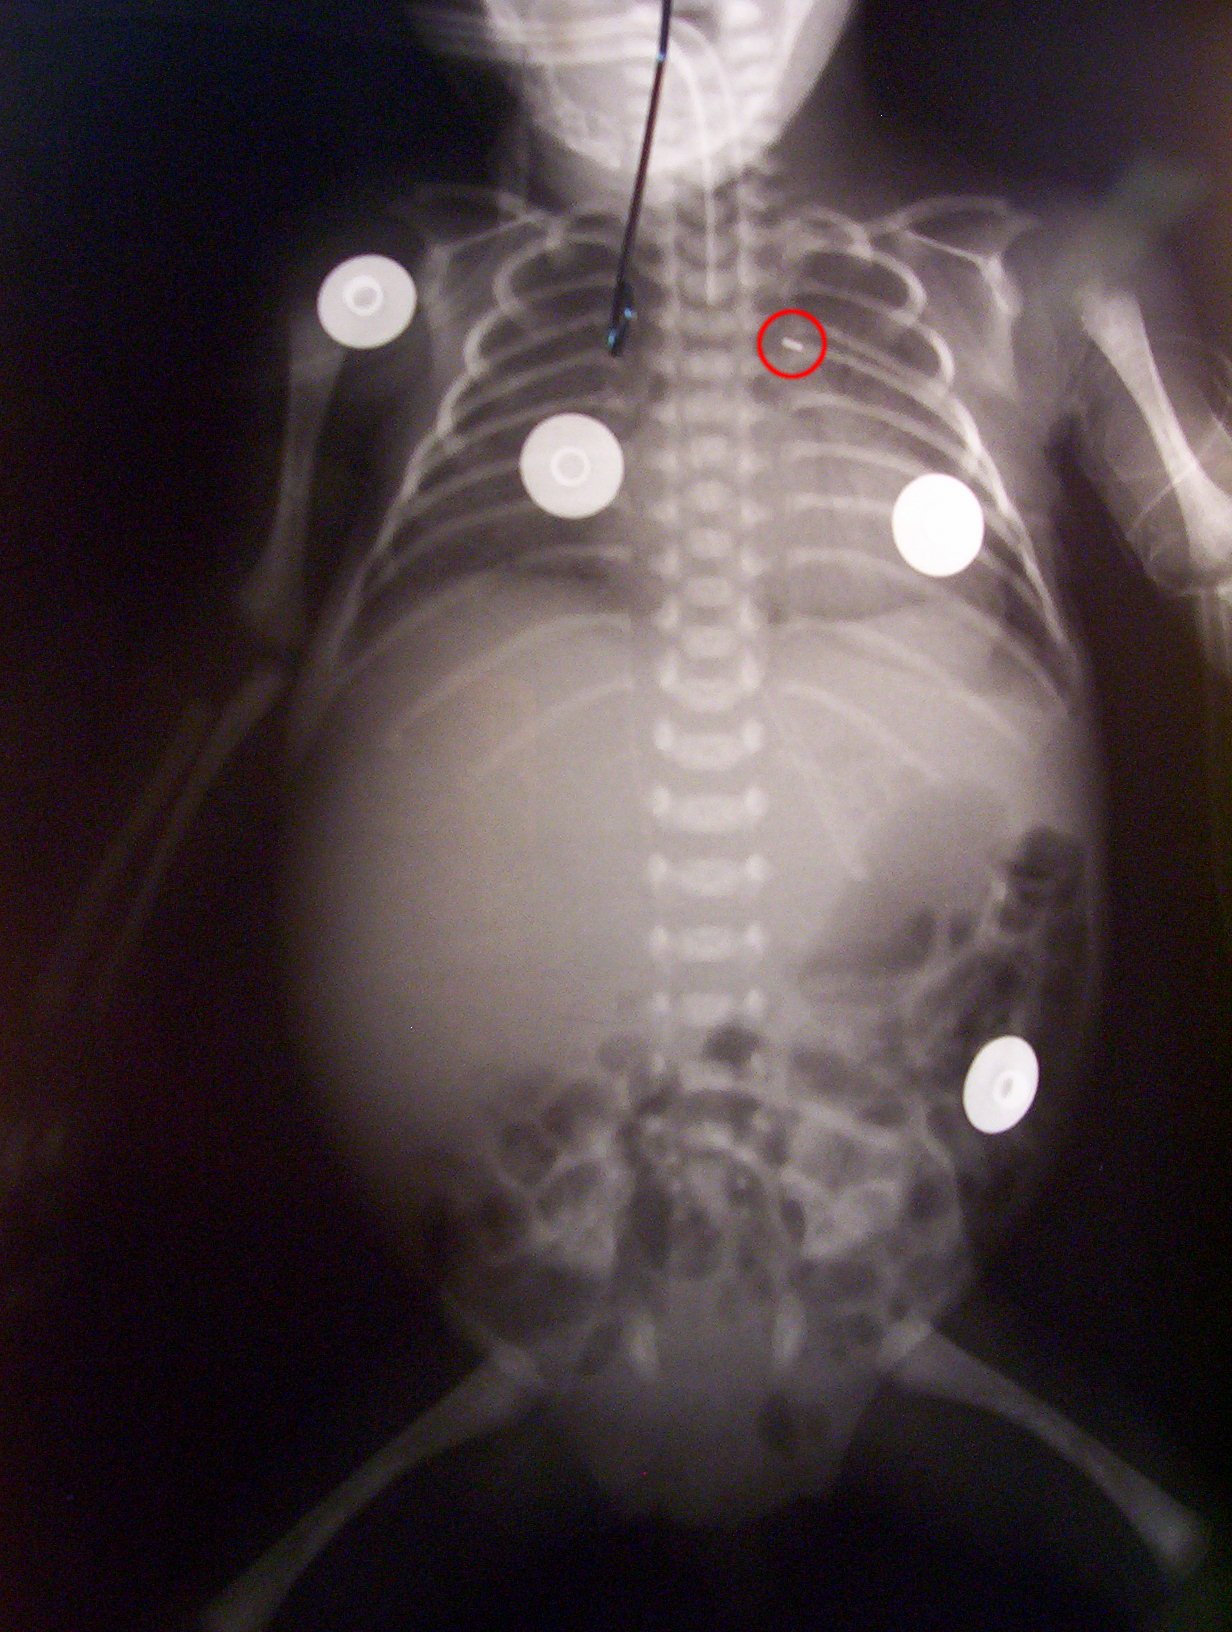

Cuando nos íbamos estaba el cirujano cardiovascular mirando esta

radiografía. El círculo rojo indica el clamp que le han puesto,

que supuestamente se reabsorve.